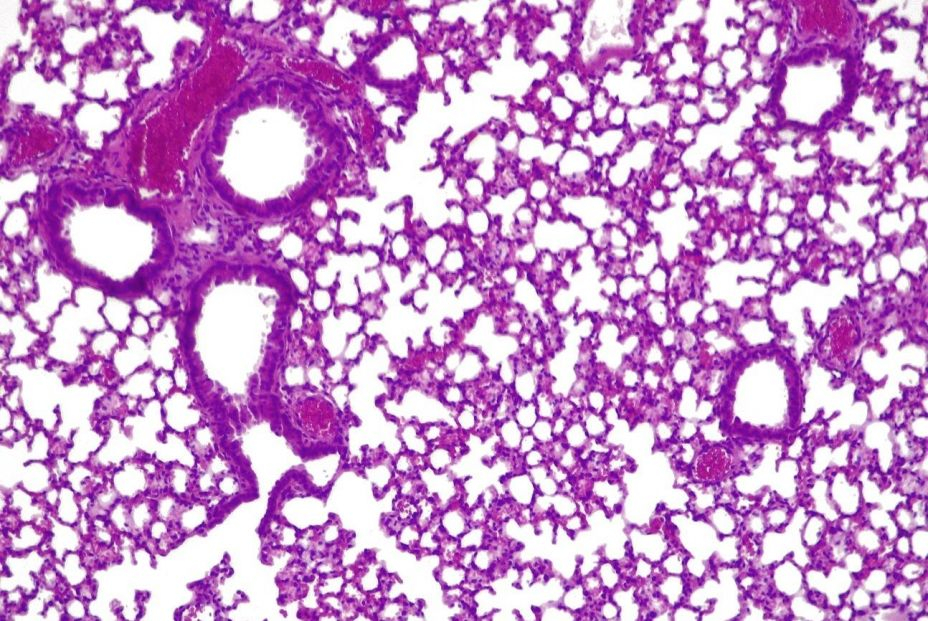

El tratamiento, cuyo estudio se ha publicado en la revista Nature Biotechnology, consiste en usar una versión modificada de la bacteria 'Mycoplasma pneumoniae' eliminando su capacidad patógena y adaptarla para que, en su lugar, ataque a 'presudomonas aerugionosa'.

La bacteria modificada se usa en combinación con dosis bajas de antibióticos que no serían eficaces por sí solas, y los científicos observaron que el uso del tratamiento en ratones redujo significativas las infecciones pulmonares.

Una vez que el tratamiento hubo terminado su curso, el sistema inmune innato eliminó las bacterias modificadas en un periodo de cuatro días.